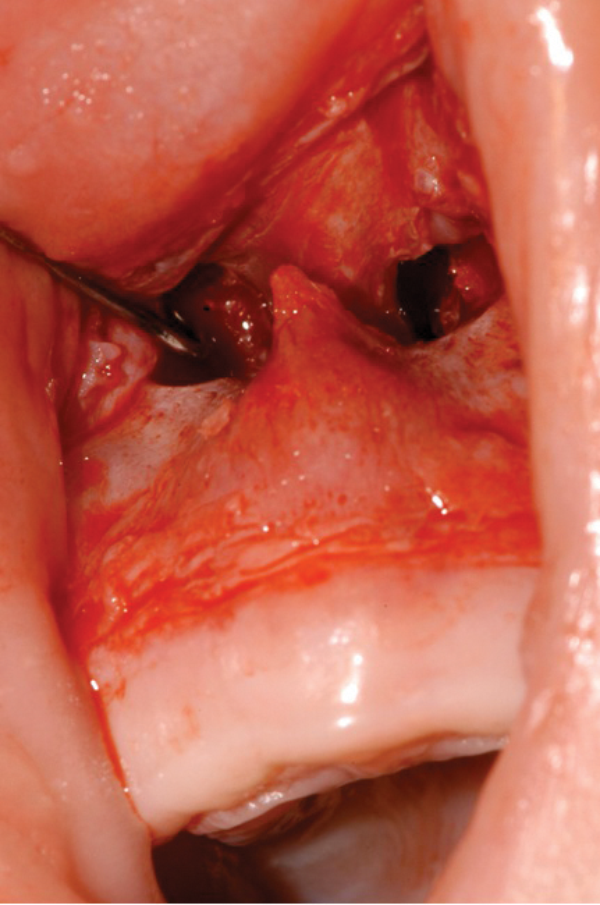

Figure 3: A mucoperiosteal flap is raised to expose the bony stenosis bilaterally.

- A mucoperiosteal flap is raised to expose the bony stenosis bilaterally (Figure 3).